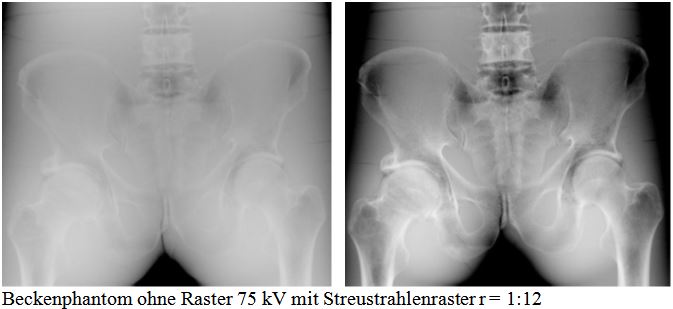

Ein Streustrahlenraster ist eine Vorrichtung in der Röntgentechnik, die vor dem Bildempfänger (Bildschirm, Detektor oder Film) angebracht ist und den Einfall von Streustrahlung auf diesem reduziert. Dadurch wird der Kontrast des Röntgenbildes erhöht.

Die im Patienten erzeugte Streustrahlung führt zu kontrastarmen, verrauschten Bildern, die ohne Zusatzmaßnahmen diagnostisch nicht auswertbar sind. Sie trägt zwar zur Filmschwärzung mit bei, ist aber weitgehend unerwünscht, da sie wie ein Schleier über dem Primärstrahlenbild liegt.

Die Folge hoher Streustrahlenanteile ist ein erheblicher Kontrastverlust, bzw. Grauschleier („Nebel“), der so groß sein kann, dass geringe Schwächungsunterschiede im Objekt nicht mehr im Röntgenbild zu erkennen sind.

Bei einer Feldgröße von 700 cm² ,d.h. einem Format von 24 cm * 30 cm und einer Objektdicke von 20 cm sind mehr als 80% der auf die Kassette fallende Strahlung, Streustrahlung, d.h. nur etwa 20 % der einfallenden Strahlung tragen zum Bildaufbau bei.

Die Bildqualität kann man verbessern, indem man das durchstrahlte Volumen möglichst klein hält, z.B. durch Einblendung und oder Kompression. Diese Maßnahme allein reicht nicht aus, um den Anteil an Bild verschlechternder Streustrahlung in erträglichen Grenzen zu halten. Das ist nur mit Hilfe eines Streustrahlenrasters möglich, im folgendem kurz „Raster“ genannt.